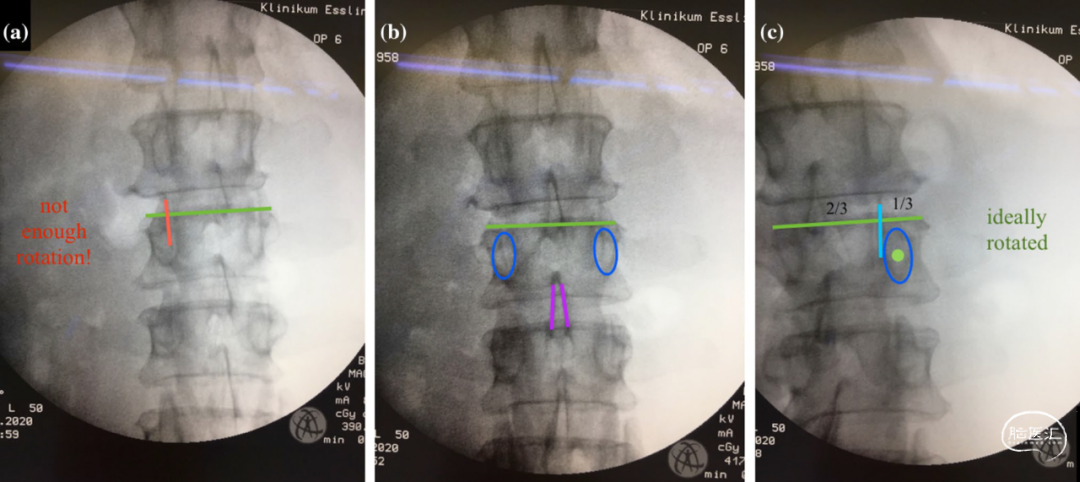

侧卧位旋转手术台10-30°(而不是C臂转动)也可在隧道视图指示下放置椎弓根螺钉(图3、4、5、6)。

图4. L1-L3椎骨的术前成像。a. 显示左侧上排椎弓根的隧道视图。旋转程度不够,上关节面(红线)与椎弓根阴影相交。手术台需要更多的旋转。b. 显示L2的真实前后位。c. 显示具有理想旋转程度的右侧下排椎弓根的隧道视图。